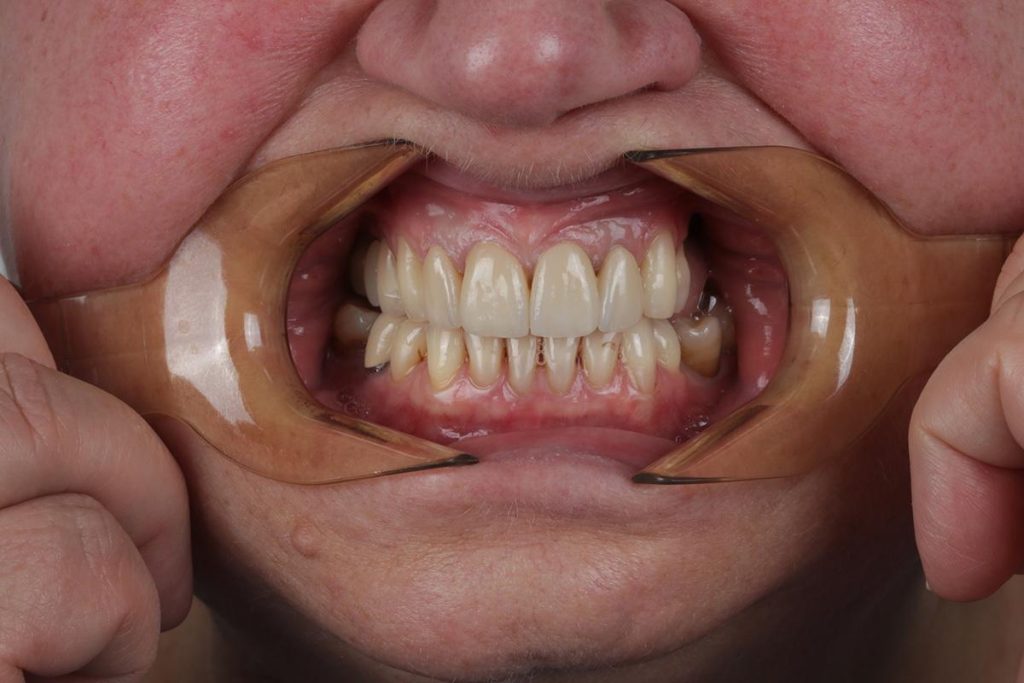

Przeprowadziliśmy precyzyjne leczenie implantologiczne, wszczepiając 11 implantów w szczęce i żuchwie. Konieczna była też regeneracja kości. Po 6 miesiącach gojenia nastąpiła odbudowa pełnołukowa. Kształt, kolor i ustawienie zębów zostały dobrane oraz wykonane na indywidualne życzenie Pacjenta.

Leczenie chirurgiczne i implanto-protetyczne przeprowadził lek.stom. Michał Badowski.